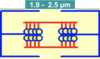

Give the contractile components of the myocardium

- Heart muscle fibres (working fibres)

- Stretching enhances their force-generating capability

Give the non-contractile components of the myocardium

- Serially attached elastic elements (SEC)

- Parallelly attached elastic elements (PEC)

- Collagen